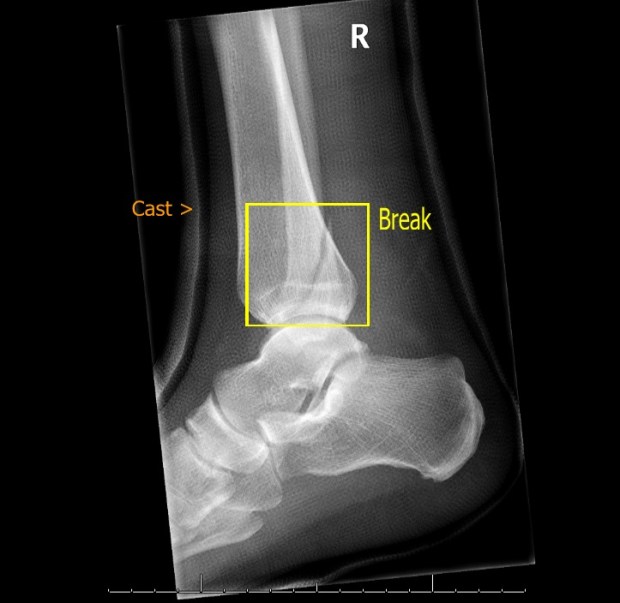

Ten years ago, I broke my leg quite badly. It required surgery, and they screwed the bone back together with bits of metal.

It never really gives me problems these days, but any injury to the same leg gets me wondering and even worrying: Have I done something to the screws? Am I going to have to go through all of that again?